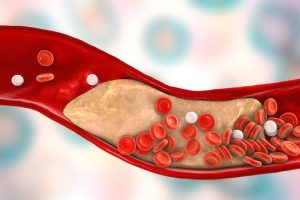

Acute coronary syndrome is generally caused by the build-up of fatty deposits (plaque) in the veins and arteries leading into the heart, more specifically the coronary arteries. When plaque develops on the walls of the arteries, there is an increased risk that it can break off, causing the blood vessel to rupture or forming a clot within the vessel. This causes the decreased or blocked flow of blood to the heart. If the arteries become too narrow due to the build-up of plaque, blood flow can also become significantly decreased, even without a clot.